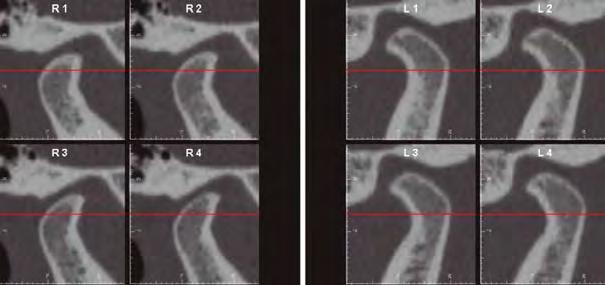

–Corticotomías y Ortodoncia. Ampliando límites del movimiento dental, por la Dra. Aranzazu Senosiain y cols. [50]